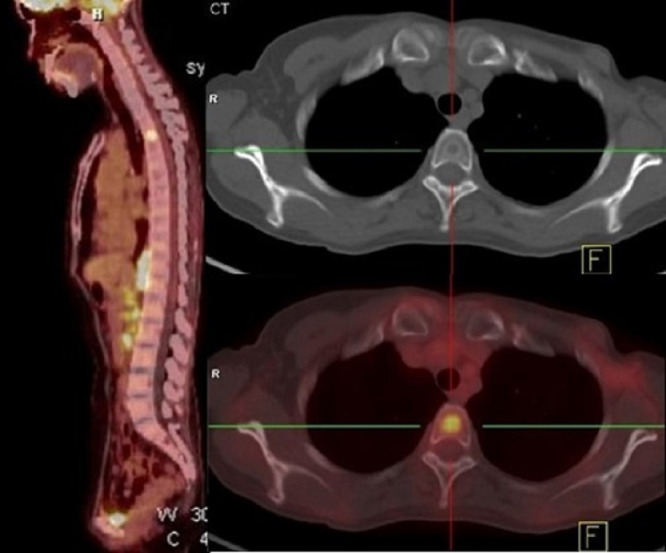

Of the 102 patients with only one bone containing a metastasis, 8 (7.8%) had head and neck tumors, 59 (57.8%) had thorax tumors, 17 (16.7%) had abdominal tumors and 18 (17.6%) had pelvic tumors. As is show in the Fig. 2, one breast cancer patient had only one bone metastasis in the thoracic spine (T3). Among these patients, no patient had only skull metastasis, 4 (3.9%) had only cervical spine metastasis, 48 (47.1%) had only thoracic bones metastasis, 13 (12.7%) had only lumbar spine metastasis, and 37 (36.3%) had only pelvis metastasis.

Fig. 2.

PET/CT images of a patient with breast cancer who had only one bone metastasis, in her thoracic spine (T3).